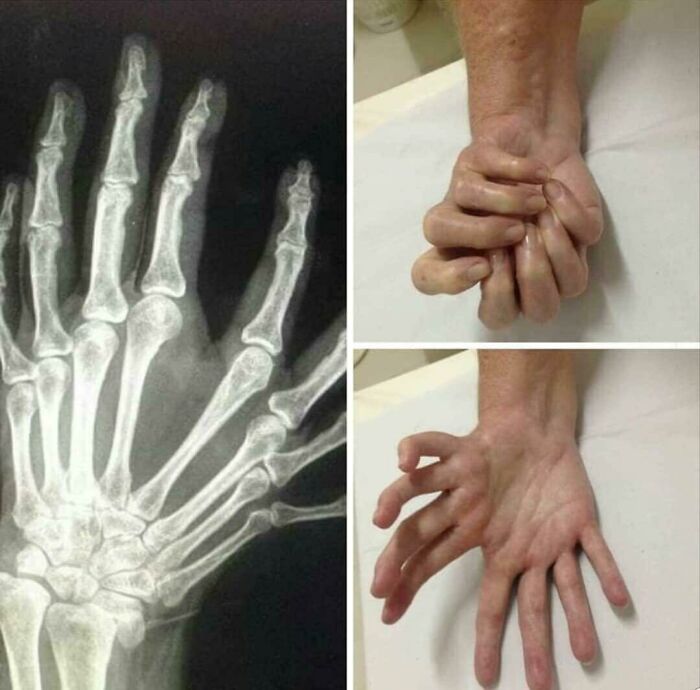

#21 Triphalangeal Thumb (Tpt) Is A Congenitalmalformation Where The Thumb Has Three Phalanges Instead Of Two. The Extra Phalangeal Bone Can Vary In Size From That Of A Small Pebble To A Size Comparable To The Phalanges In Non-Thumb Digits.

Image credits: Surgeox